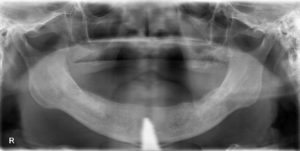

【術前】

カウンセリングの結果、今お使いの入れ歯が合わず、インプラントを併用した外れない入れ歯をご希望され、本日インプラント手術を行いました。